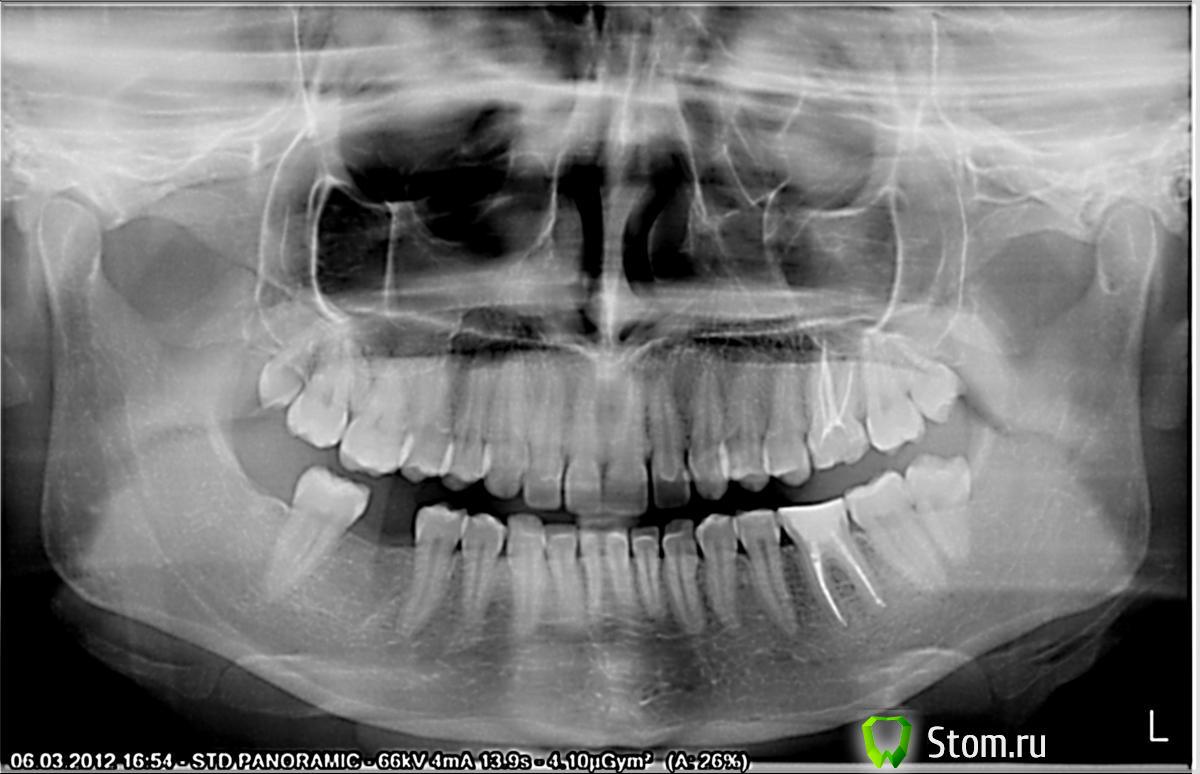

Korn05 Опубликовано 19 апреля, 2012 Поделиться Опубликовано 19 апреля, 2012 (изменено) Здравствуйте.Есть проблема с шестерками на той стороне, где нет отсутствующих зубов - с верхней и нижней. У обеих каналы были вроде как "нормально" пролечены 2-4 месяцев назад (на одном -4, на другом - 2 месяца.), и обе периодически неприятно побаливают, из-за чего откладываю коронки. В нижней шестерке боль есть только при надавливании зуба сбоку и редко при накусывании, реже - просто так.В верхней - часто тянущая слабая боль, к которой уже даже стал немного привыкать. Обостряется при попадании на зуб холодного, горячего, особенно - при надавливании. Два разных врача смотрели снимки, сказали что все нормально, и что болеть ничего не должно, но тем не менее БОЛИТ уже месяцами. Что делать? куда идти? Врачи говорят, что все ок, и соответственно делать тут нечего, по их мнению. От этого бессилие и растерянность - врачи говорят, что не должно болеть, но я-то знаю, что болит, и вообще непонятно что делать. Уже потрачена куча денег на лечение (один зуб перелечивался дважды) и идти в 3-ий раз куда-то перелечивать уже просто нет денег. Ну только если бы знал, что 100% все проблемы пропадут после этого, то нашел бы деньги.Пожалуйста, дайте совет. Данного снимка достаточно? Или нужно сделать другие снимки? (отдельные снимки каждого зуба на фото-бумаге получились плохие, почти ничего не видно на них). Изменено 19 апреля, 2012 пользователем Korn05 Ссылка на комментарий

Magdalena Опубликовано 19 апреля, 2012 Поделиться Опубликовано 19 апреля, 2012 Добрый вечер. Лучше посмотреть отдельные снимки зубов. Возможно в верхнем 6 зубе пропущен канал, там обычно 4 канала. Лучше всего дополнительный канал виден на 3Д-компьютерной томограмме. Ссылка на комментарий